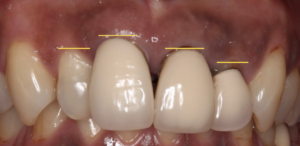

最初の状態がこちらです。

前歯には3本被せ物がしてある状態でした。

このまま、被せ物だけを変えることもできますが

より理想的な状態まで改善していく為のポイントは

歯頚ラインとは前歯の歯茎の並びと言い換えるとわかりやすいかもしれません。

左右でこのラインが不揃いなのがわかります。

ここが整っているとより美しく、かつ、歯磨きも

しやすくなりますので虫歯や歯周病の予防にも、繋がります。

このように、とても調和の取れたバランスの良い前歯になりました。

前歯の被せ物を交換するだけではこの自然感は得られません。